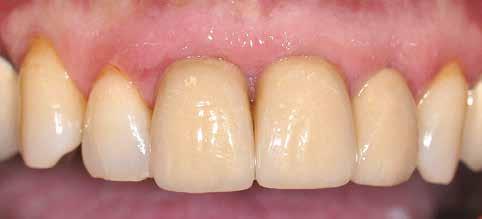

A gyógyulási időszakot követően a csontos gyógyulás ellenőrzése és az implantáció tervezése céljából állcsonti CT-felvételt készítettünk. A CT-felvételen tökéletes csontos gyógyulást észleltünk, az alveoláris csont volumene

Fergeteges

teljes mértékben megtartott, a vertikális augmentáció a tervezettnek megfelelő eredményű volt (13–15. ábra), a klinikai kép is ennek megfelelően alakult, optimális menynyiségű keratinizált ínnyel és azt adekvát sebészi technika eredményeképpen megtartott vesztibulummal (16–17. ábra). Az alsó és felső állcsontba 4-4 darab Bredent COPA Sky implantátumot ültettük, D1-D2 csontminőség mellett,

35 Ncm primer stabilitást mértünk. Nyílt gyógyulási protokollt alkalmazva az ínyformázókat is behelyeztük, amelyek körül az ínyt csomós öltésekkel zártuk (18–20. ábra) Amennyiben lehetséges, mindig nyílt gyógyulási protokollt választunk, így biztosítva elegendő időt a lágyrészek maturációjához (29). Kiemelendő, hogy az irodalmi adatoknak (30, 31, 32) és saját tapasztalatunknak megfelelően az íny biotípusának jelentős, pozitív irányú változását észleltük. Az implantátumokra 180 nap gyógyulási időszakot követően (minden implantátum stabilitása Periotesttel –8-as értékű volt) hagyományos lenyomatvételi módszer és egyéni értékű artikulátor használatával a fogtechnikus (D1 Dental Kft., Garamvári Csaba) overdenture típusú fogpótlást készített (21. ábra)

A protetikai rehabilitációt követően 9 hónappal az alveoláris struktúrák stabilak, a röntgenfelvételen a csontállomány megtartott, a beteg panaszmentes, rágó funkciója kifogástalan, az esztétikai eredménnyel teljes mértékben elégedett (22–23. ábra)